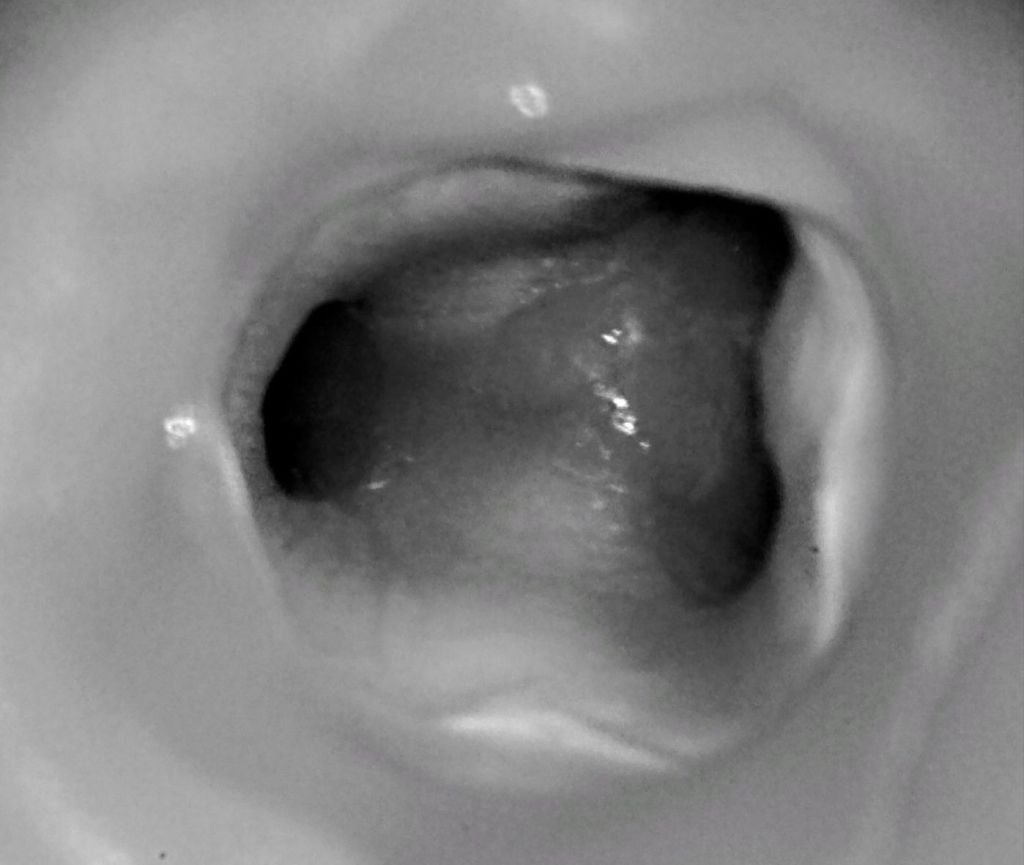

A mikroszkóp használatával, a nagyítás maximumán (25x) dolgozva betekintést nyerünk egy új, korábban láthatatlan világba, hiszen sok esetben egészen a gyökércsúcsig leláthatunk és észlelhetünk egyéni anatómiai variációkat a gyökércsatornák számát, lefutását, elágazásait illetően. Mindez nagyban befolyásolja a kezelés hosszútávú sikerességét, hiszen végeredményben a nem megtalált és nem kitisztított csatornák miatt történik manapság a legtöbb foghúzás.

- A mikroszkóp akár 25-szörös nagyítást biztosít, így az orvos sokkal pontosabban láthatja a gyökércsatornákat, rejtett elágazásokat, repedéseket vagy korábban nem kezelt csatornákat.